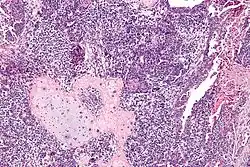

Carcinosarcome

Le carcinosarcome est une tumeur maligne associant des aspects carcinomateux et sarcomateux[1]. Il est fréquemment de localisation utérine.